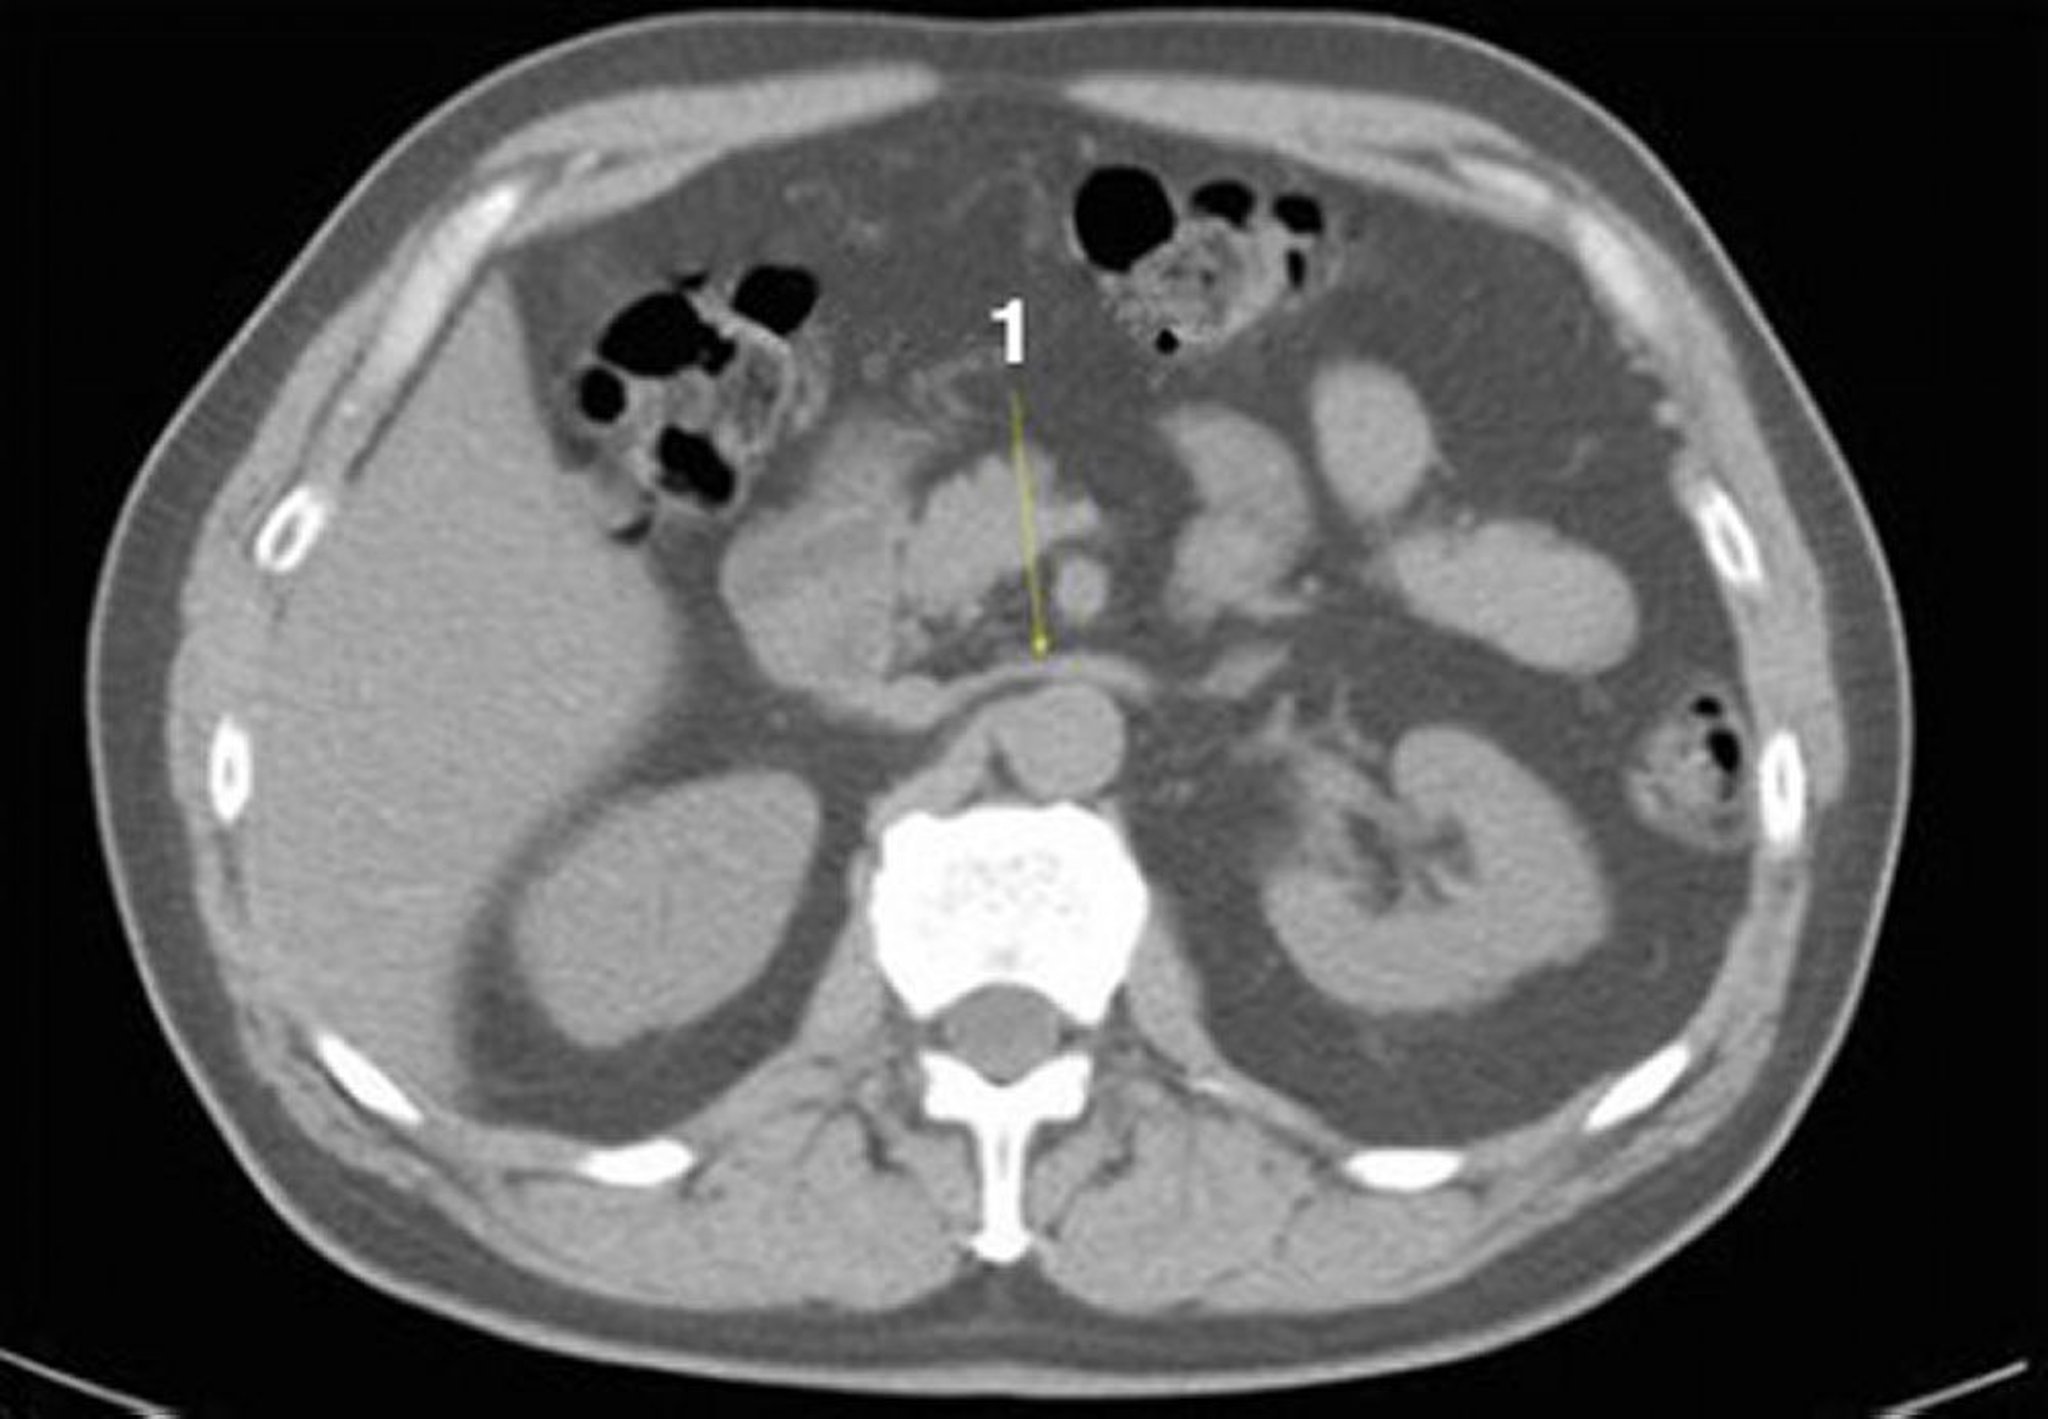

TDM sans contraste de l'abdomen et du bassin montrant une anatomie normale (diapositive 12)

1 = veine rénale gauche.